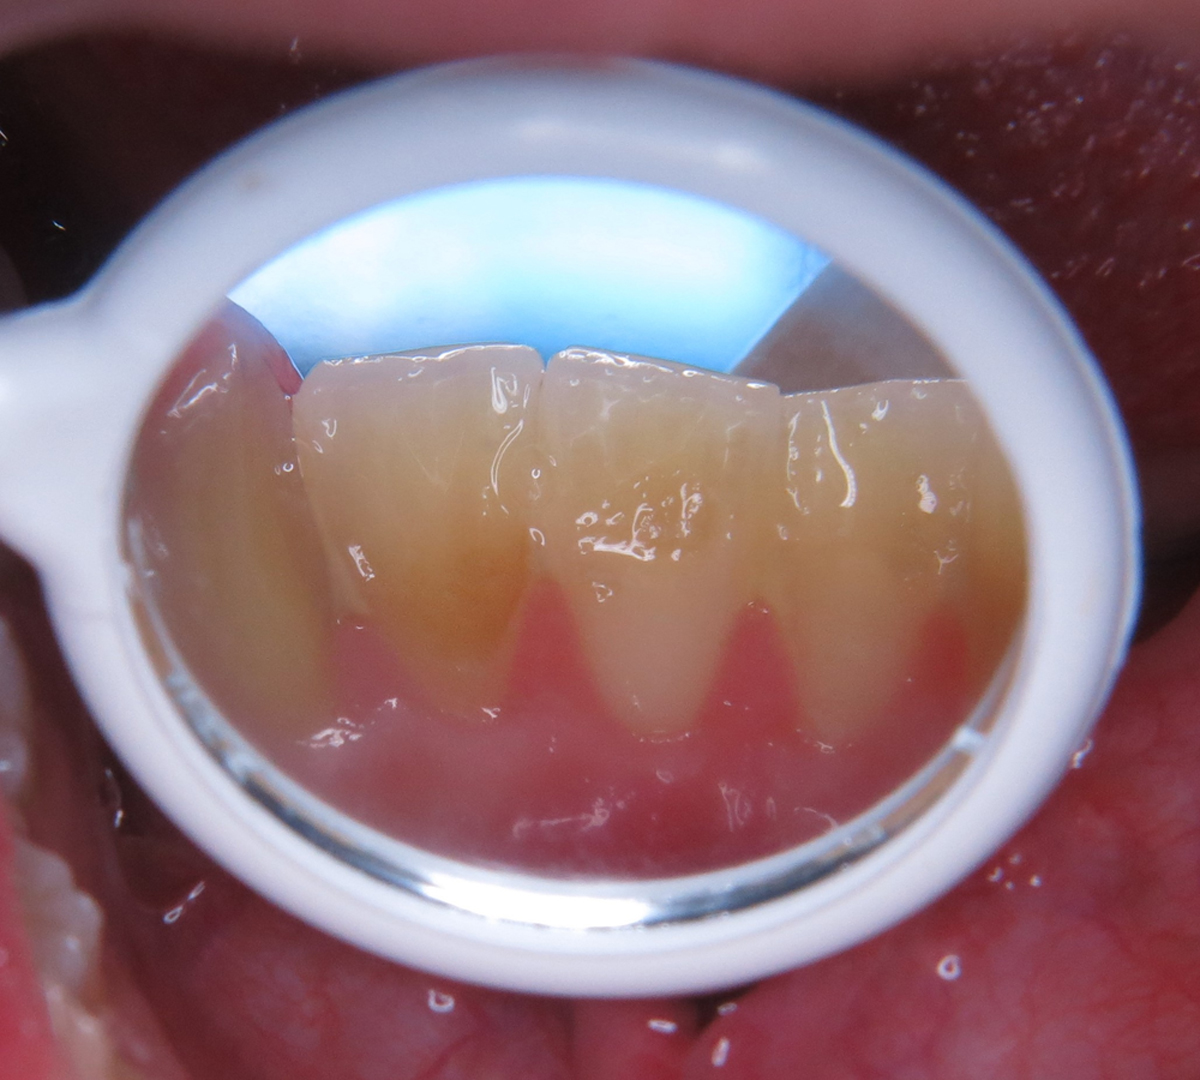

Fig. 2

Six-month postoperative healing of the giant cell fibroma: no evidence of recurrence.